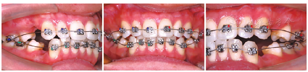

1.上、下颌前牙及第一磨牙粘接MLF托槽及XBT颊面管,上、下颌放置0.014~0.016英寸(1英寸=2.54厘米)Cu-NiTi排齐前牙,维持支抗(图2)。

2.待前牙基本排齐后,粘接第二前磨牙托槽和第二磨牙颊面管,上、下颌顺序更换0.018英寸~0.018英寸×0.025英寸NiTi丝,排齐牙列,整平下牙列。

3.于上颌双侧颧牙槽嵴区植入支抗钉,上、下颌换0.018英寸×0.025英寸不锈钢方丝,并于上颌双侧侧切牙远中弓丝放置长牵引钩,下颌双侧侧切牙远中弓丝放置短牵引钩,上颌用拉簧行支抗钉至牵引钩牵引内收前牙关闭间隙,下颌行第一磨牙至牵引钩皮链牵引内收关闭间隙(图3)。